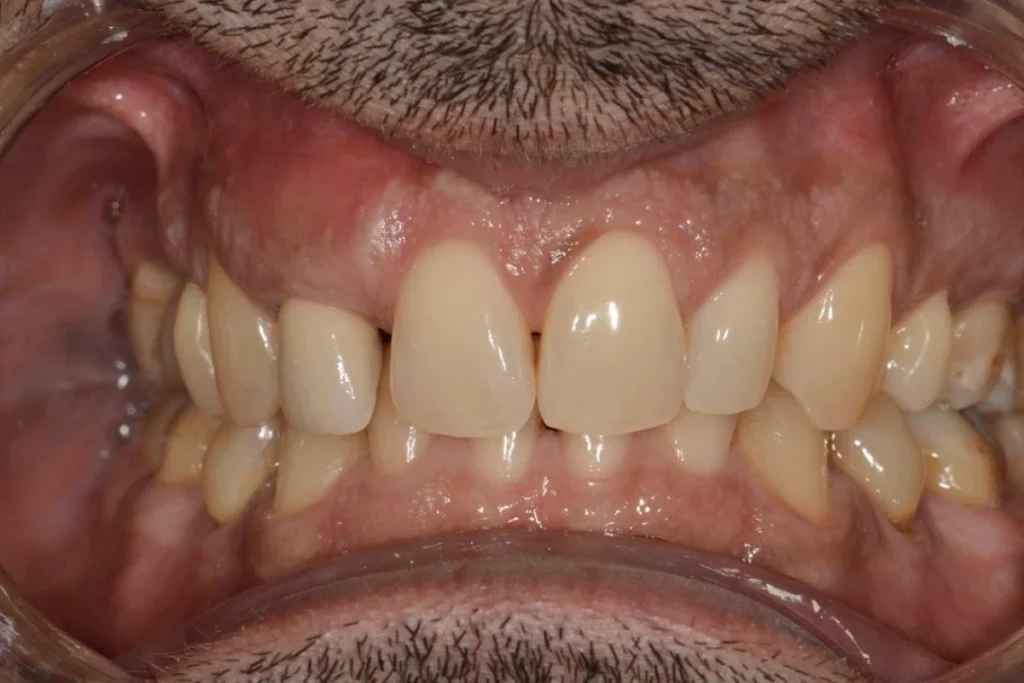

Mr C. 40 ans vient nous consulter pour une visite de routine. L’examen clinique et met en évidence un infection sous une dent couronnée il y plusieurs années par un confrère. Le scanner réalisé au cabinet confirme la nécessité d’extraire cette dent et nous décidons de réaliser un protocole d’extraction implantation et mise en esthétique immédiate.

En clair, nous réalisons l’extraction de la dent, la mise en place de la racine artificielle ou implant et la fabrication d’une couronne provisoire en résine le tout lors de la même séance. Le patient repart du cabinet avec toutes ses dents!

Dans le cas présent, nous avons même pu répondre à la demande esthétique du patient en symétrisant son incisive latérale droite avec celle de gauche. L’intervention est réalisée sous anesthésie locale ce qui la rend parfaitement indolore.

Ce type de protocole est réalisé systématiquement au cabinet lorsque la situation nous le permet afin d’éviter à nos patients la galère d’un appareil provisoire amovible pour remplacer la dent absente. En contrepartie, le patient s’engage à respecter nos recommandations post opératoires pendant les semaines qui suivent l’intervention.